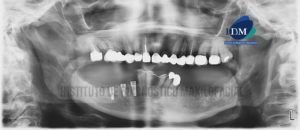

Paciente sexo femenino de 55 años acude al Instituto de Diagnóstico por Imágenes para evaluación imagenológica previa a la confección de guía quirúrgica. A la